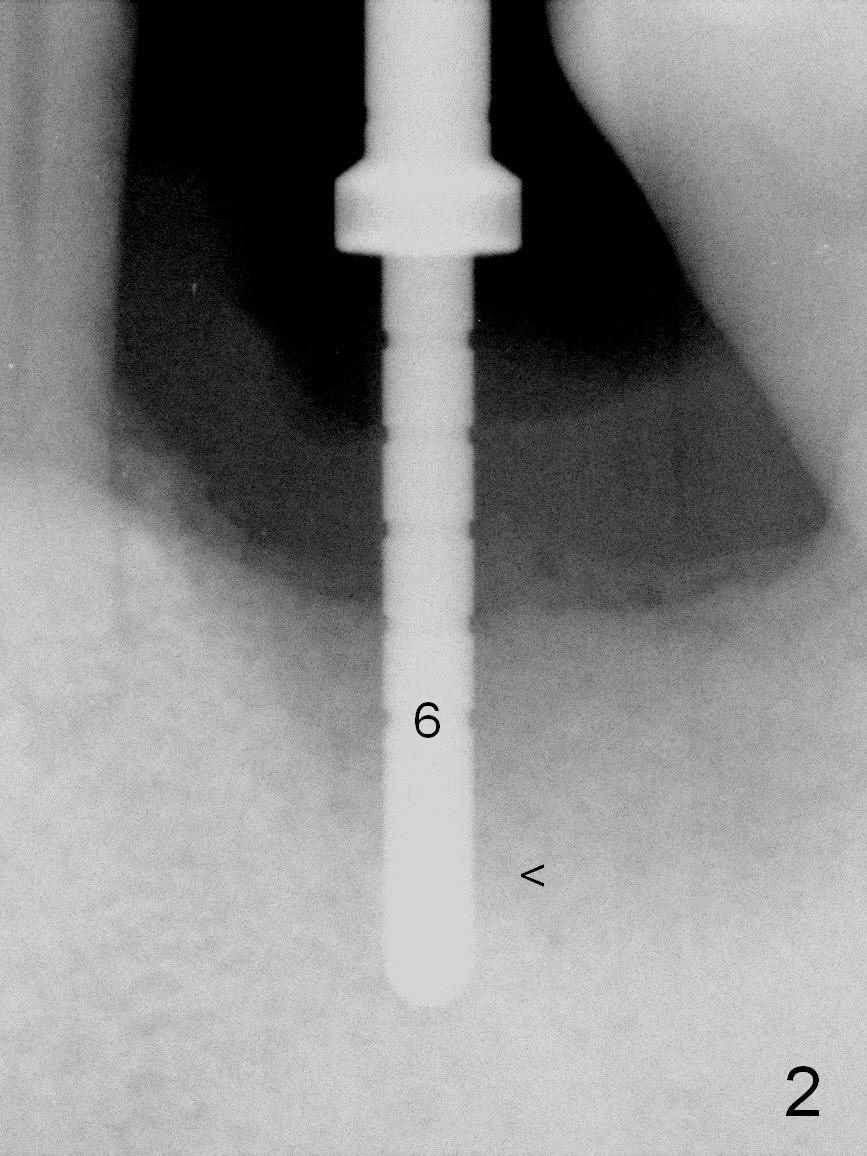

When the patient returns for #19 extraction and immediate implant, there is buccal (Fig.1 *) and lingual gingival swelling. The distobuccal root is exposed (D). Both the buccal and lingual walls are low. There is no septum. After removal of granulation tissue, an osteotomy is established in the bottom of the socket (slightly mesiolingually). The depth is approximately 3 mm in new bone (half of 6 mm and arrowhead). When the depth increases approximately 6 mm in new bone (Fig.3 arrowhead with 6x20 mm tap (T) in place), the Inferior Alveolar Canal is still invisible in PA. Panoramic X-ray has to be taken (Fig.4). So far infiltration anesthesia has been administered. When #2 sensor is inserted in the lingual vestibule, the patient feels pain and nausea. Lingual Nerve block is provided. The patient feels pain when further osteotomy is carried on. Since the depth of the osteotomy is confirmed by panoramic X-ray, Inferior Alveolar Nerve block is added. A 6x17 mm tissue-level implant is placed with clearance from the Inferior Alveolar Canal (Fig.5: red dashed line: the superior border of the Canal). Therefore, Lingual Nerve block allows lower placement of sensor so that the Inferior Alveolar Canal is detectable by PA.